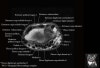

- Sagittal section

Sagittal T1 evaluates the tendons, bone marrow and relationships between the osseous structures.